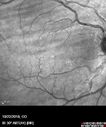

Congenital Hypetrophy of the Retinal Pigment Epithelium (CHRPE)621 views63 year old female with normal vision and CHRPE lesion in the right eye.Apr 27, 2020

Congenital Hypetrophy of the Retinal Pigment Epithelium (CHRPE)381 views63 year old female with normal vision and CHRPE lesion in the right eye.Apr 27, 2020

Congenital Hypetrophy of the Retinal Pigment Epithelium (CHRPE)365 views63 year old female with normal vision and CHRPE lesion in the right eye.Apr 27, 2020

Congenital Hypetrophy of the Retinal Pigment Epithelium (CHRPE)375 views63 year old female with normal vision and CHRPE lesion in the right eye.Apr 27, 2020

Congenital Hypetrophy of the Retinal Pigment Epithelium (CHRPE)376 views63 year old female with normal vision and CHRPE lesion in the right eye.Apr 27, 2020

Congenital Hypetrophy of the Retinal Pigment Epithelium (CHRPE)432 views63 year old female with normal vision and CHRPE lesion in the right eye.Apr 27, 2020